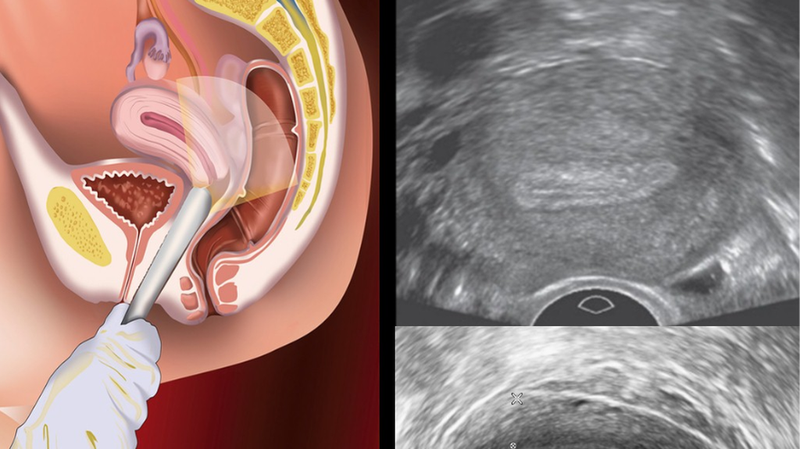

Siêu âm trực tràng, còn có tên gọi khác là siêu âm ngã trực tràng và siêu âm đầu dò trực tràng. Đây là phương pháp chẩn đoán hình ảnh rất được ưa chuộng nhờ có độ chính xác cao và hạn chế xâm lấn tối đa. Siêu âm qua ngã trực tràng được thực hiện bởi các bác sĩ giàu kinh nghiệm, đã được đào tạo bài bản và có nhiều năm thực hành.

Nguyên lý hoạt động của siêu âm đầu dò cũng giống như các hình thức siêu âm khác. Bác sĩ sẽ dùng một đầu dò chuyên dụng cùng với song siêu âm (sóng có tần số cao) đưa qua trực tràng để khảo sát các cơ quan trong vùng bụng dưới. Chẳng hạn như tử cung, buồng trứng, túi tinh,... Sau khi phát sóng siêu âm, hình ảnh thu nhỏ của các cơ quan này sẽ được hiển thị trên màn hình.

Phương pháp siêu âm đầu dò sẽ giúp khảo sát các thông số như hình dáng, kích thước, chuyển động dòng máu và cấu trúc mô trong của nội tạng. Dựa trên những thông tin này, các bác sĩ sẽ đưa ra những đánh giá rõ ràng và chính xác hơn về tình trạng của bệnh nhân. Hơn nữa, so với các phương pháp siêu âm truyền thống, siêu âm đầu dò trực tràng sẽ cho hình ảnh rõ nét và chi tiết hơn.